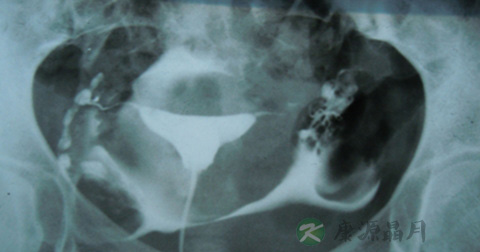

1、输卵管通而不畅:推注造影剂有阻力,造影剂进入盆腔缓慢,在停注造影剂十数分钟后,可见造影剂在盆腔内弥散,但弥散欠佳。

2、输卵管积水:造影剂积聚在输卵管内,输卵管异常扩张呈囊状或腊肠状,以远端明显,多伴有输卵管伞端阻塞。盆腔内一般无造影剂影弥散。

3、输卵管通畅:子宫充盈呈倒三角形,两侧输卵管像细虫样弯曲在子宫两侧,造影剂先充盈输卵管近端的狭部,然后迅速向壶腹端部充盈,继而自伞端弥散至盆腔。